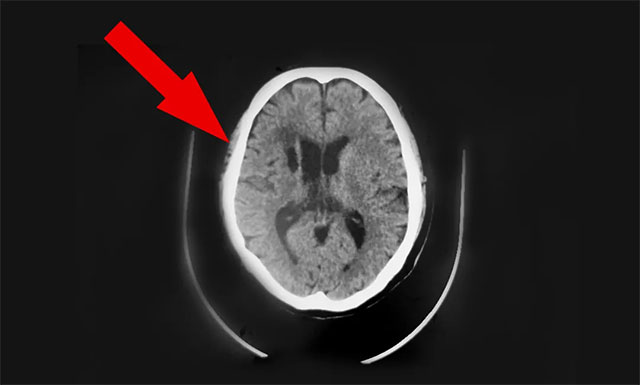

近期,因头晕不适感持续,前往上海某医院就诊检查。行头颅CT发现:1. 两侧半卵圆中心区及基底节区多发腔隙性脑梗塞;2. 左小脑及右侧基底节区斑片软化灶;门诊拟以“颈内动脉狭窄、脑梗死”收入。治疗一个月后无明显改善。为求进一步治疗,9月中旬胡夫人陪同患者胡某慕名转往上海蓝十字脑科医院,由6B神经外科潘仁龙主任接诊。

在潘仁龙、吴志群及黄秀夫三位医生会诊下,基于患者近半个月主诉有头晕,偶有行走不稳,头晕症状明显,次数较前明显增加。9月16日CT头颅CTA+CTP 示病患右侧大脑中动脉M1段、左侧大脑后动脉多处狭窄,右侧大脑中动脉中央、远端分支明显稀疏、减少等;考虑心脏支架术后状态,基础性疾病较多,颅内多发血管性狭窄,行血管搭桥手术风险较高,建议行颞肌贴敷术,以改善患者病情,提高患者生活质量,建议尽早手术治疗。